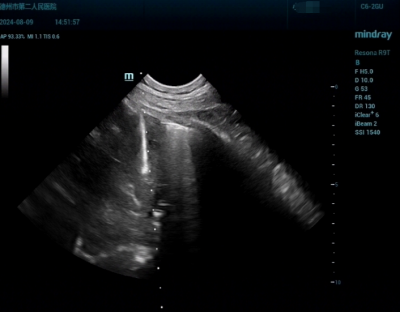

• 德州市第二人民医院:超声穿刺穿越纵隔“禁区”完成标本采样

德州市第二人民医院:超声穿刺穿越纵隔“禁区”完成标本采样

2024-09-19 09:25